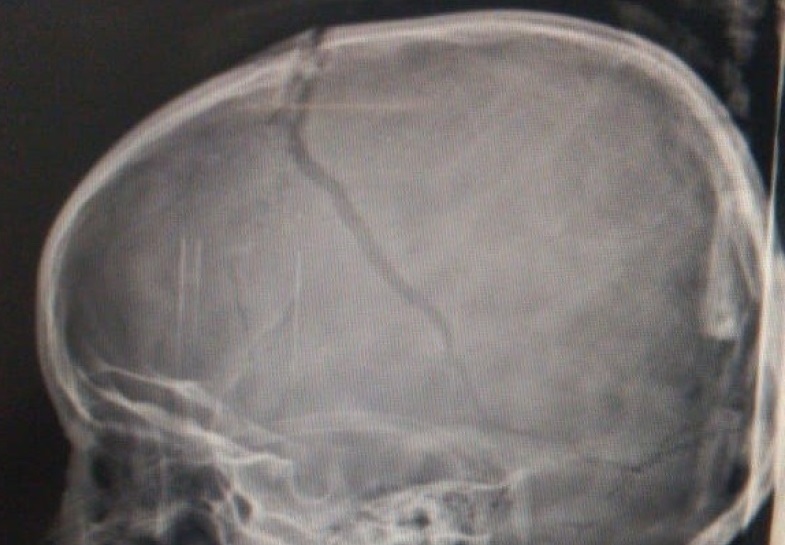

L. sofreu um grave traumatismo craniano, teve hemorragia e agora está em coma induzido. Foto: Reprodução/Arquivo da Família

L.T.A, a menina de 5 anos que caiu do toboágua no Clube Recreio Colonial, em Catalão, na tarde deste sábado (11), continua internada na Unidade de Terapia Intensiva (UTI) do Hospital de Urgências de Goiânia Governador Otávio Lage de Siqueira (HUGOL). A garota, que sofreu um grave traumatismo craniano, está em coma induzido. Apesar de ter sofrido uma hemorragia, seu estado de saúde é considerado estável. A família tem esperança que o inchaço no cérebro de L. ceda nas próximas horas.

L. caiu de uma altura de 5 metros de altura e recebeu os primeiros atendimentos de uma equipe do Corpo de Bombeiros. Foto: Facebook/Reprodução